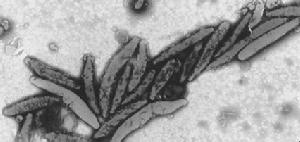

呈“S”形彎曲、弧形或稍直,偶見分支狀。一般表面較光滑,末端或二端(多數為一端)具有2~6條鞭毛,長度稍長於菌體。鞭毛外均有明顯的鞘,帶鞘的鞭毛直徑約50nm的圓球狀結構相連。菌體末端鞭毛基礎結構內側,有一寬達200nm~400nm的電子密度明顯降低區域,其底部無明顯的細胞膜結構為界。在光滑的菌體表面有進呈現大小較均勻、排列整齊的突起。